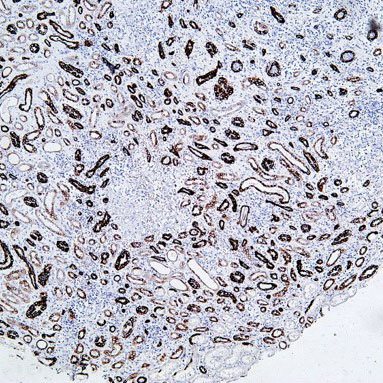

CD45 staining of paraffin-embedded human lymph node sections: Due to insufficient tissue fixation, lymphocytes at the edge of the lymph node show strong CD45 positivity, while those in the inner part of the tissue exhibit weak positivity, leading to uneven staining overall.

2 HE staining of paraffin-embedded renal tissue sections: Delayed or incomplete fixation results in blurred cell nuclei and poor contrast.